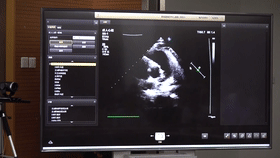

5G遠(yuǎn)程會(huì)診現(xiàn)場(chǎng),西安國際醫(yī)學(xué)中心心內(nèi)科張衛(wèi)澤主任、超聲科陳姍姍主任打開4K高清顯示器,屏幕上立刻出現(xiàn)了商洛國際醫(yī)學(xué)中心的B超畫面,一位醫(yī)生正在為患者做心臟B超,隨著探頭的轉(zhuǎn)動(dòng),超聲機(jī)器上的畫面清晰可見,雖然兩家醫(yī)院相距一百多公里,但畫面流暢,沒一點(diǎn)拖沓。

“真的太棒了”張衛(wèi)澤表示,“沒有延時(shí)與卡頓,清晰的好像在一個(gè)房間內(nèi)進(jìn)行病歷討論”。陳姍姍非常興奮,直呼很震撼。她告訴筆者,“以前做遠(yuǎn)程會(huì)診,經(jīng)常遇到畫面和聲音不在一個(gè)頻道、畫面模糊等情況,遇到疑難病歷只能將影像拷下來回去研究,現(xiàn)在好了這些問題都將一次性解決?!?/span>